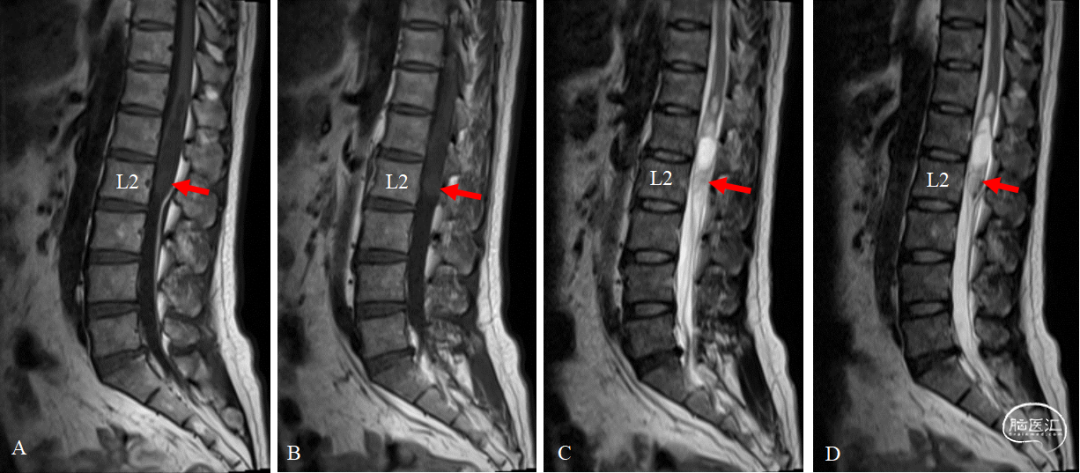

简要病史经过:患者本人诉于1年前无明显诱因出现右下肢无力跛行,偶伴有右下肢麻木症状,逐渐出现左下肢无力感。半年前患者上述症状进一步加重,并出现小便失禁,间断出现大便解不尽感。否认下肢疼痛、肿胀、虫爬感、冰凉感等。查体:下肢肤色、皮温正常,足背动脉搏动良好;神经系统查体:右下肢膝关节以下轻触觉及针刺觉减退,其余查体未见异常。辅助检查:术前MRI平扫:腰2椎体水平脊髓内可见类椭圆形实性占位(图1,红色箭头),呈混杂等T1稍长T2信号,上端脊髓囊状扩张,呈长T1长T2信号;增强序列(图2):腰2椎体水平椎管内后缘略偏右侧可见类圆形明显强化结节影,边界清晰,大小约1.73cm×1.32cm,病变与邻近硬脊膜相连,下方为终丝结构(图2,黄色箭头)。

图1. 术前MRI。A-B所示T1WI序列;C-D所示T2WI序列